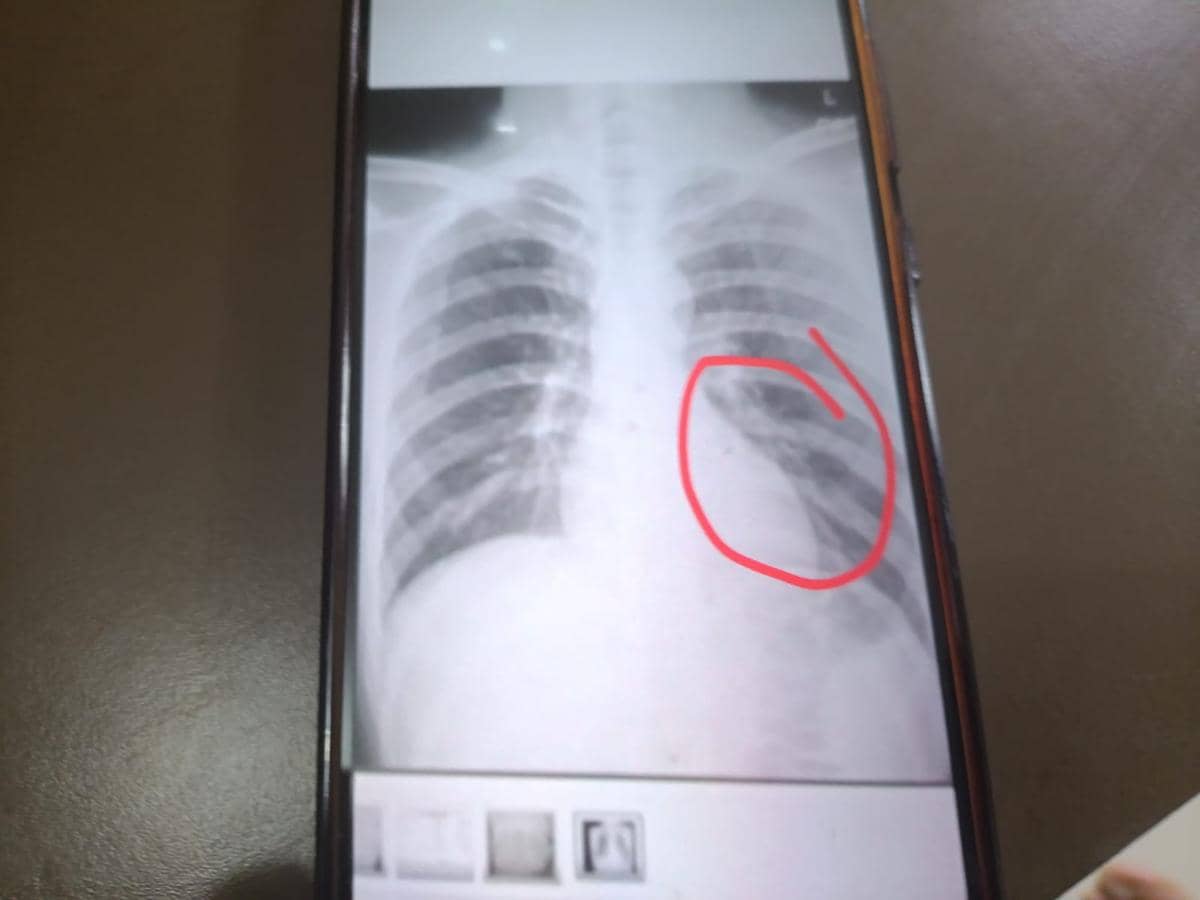

Tulungagung, IDN Times - Pengurus Askab PSSI Tulungagung mengecam keras insiden tendangan kungfu yang menimpa pemain Perseta 1970 Tulungagung, Firman Nugraha. Gelandang tersebut ditendang oleh pemain Putra Jaya Pasuruan, M Hilmi Gimnastiar dalam pertandingan yang babak 32 besar grup CC Liga 4 Jawa Timur, yang berlangsung di Stadion Gelora Bangkalan. Tindakan yang tidak menunjukkan sportivitas tersebut menyebabkan Firman mengalami retak tulang rusuk kiri bagian bawah.